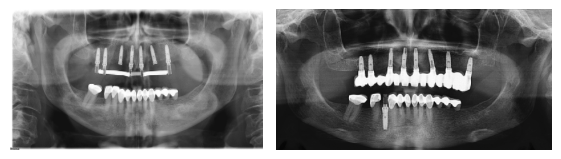

Sobredentadura maxilar y mandibular sobre 4 implantes

Paciente con enfermedad periodontal generalizada y quistes apicales.

Se le realizaron las exodoncias y la colocación de 4 implantes osteointegrados, en la misma fase quirúrgica, y se rehabilitó con dos SOBREDENTADURAS.